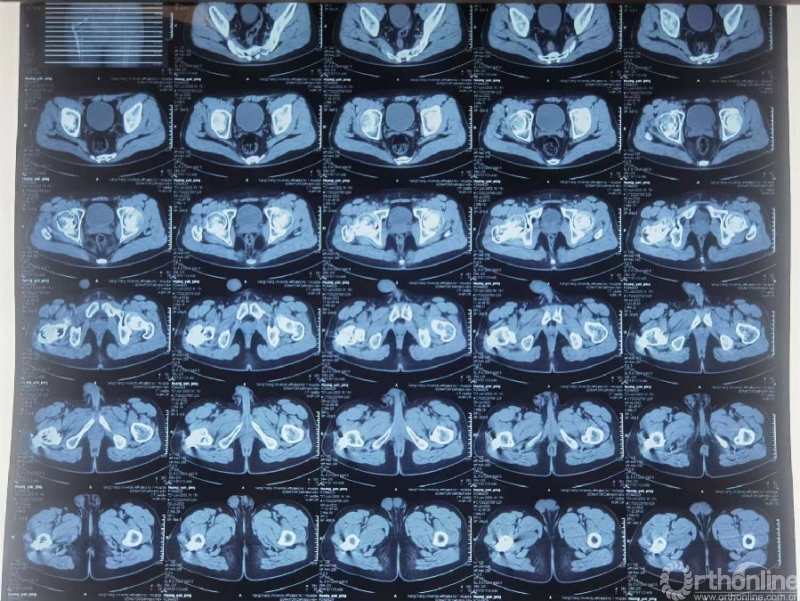

骨折术后骨不连(2022.3)

骨折术后骨不连(2022.7.3)

手术讨论:

1. 骨折不愈合原因?

骨折类型、患者因素、复位质量、手术技术…

2. 进一步处理?

保髋?

3. 保髋

翻修?内固定方式?植骨?自体骨or异体骨